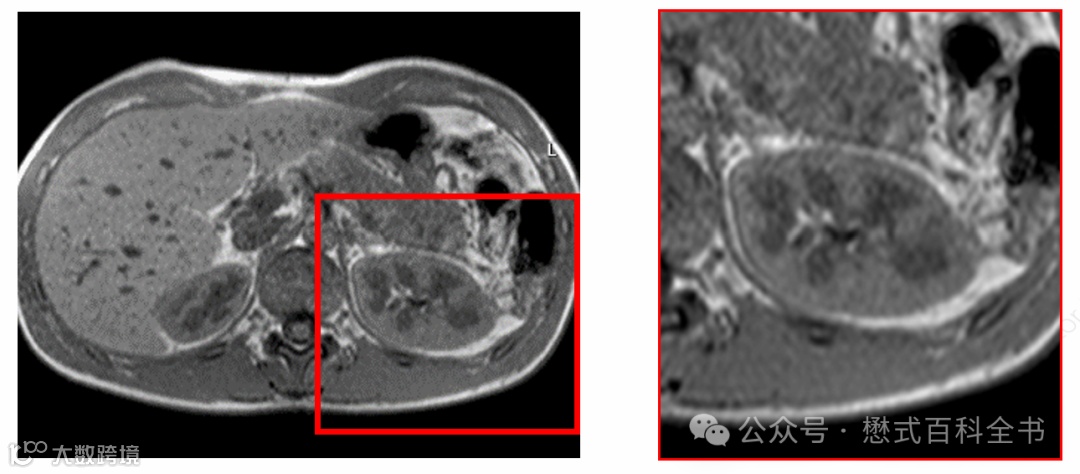

图9:T1-FLAIR(T1-IR)序列可见反弹点伪影[2]

这种伪影的表现,有时候很像是TI设置不合理导致的液体信号抑制不彻底。如同T2-FLAIR序列一样。

图10:T2-FLAIR中TI设置不合理导致脑脊液勾边